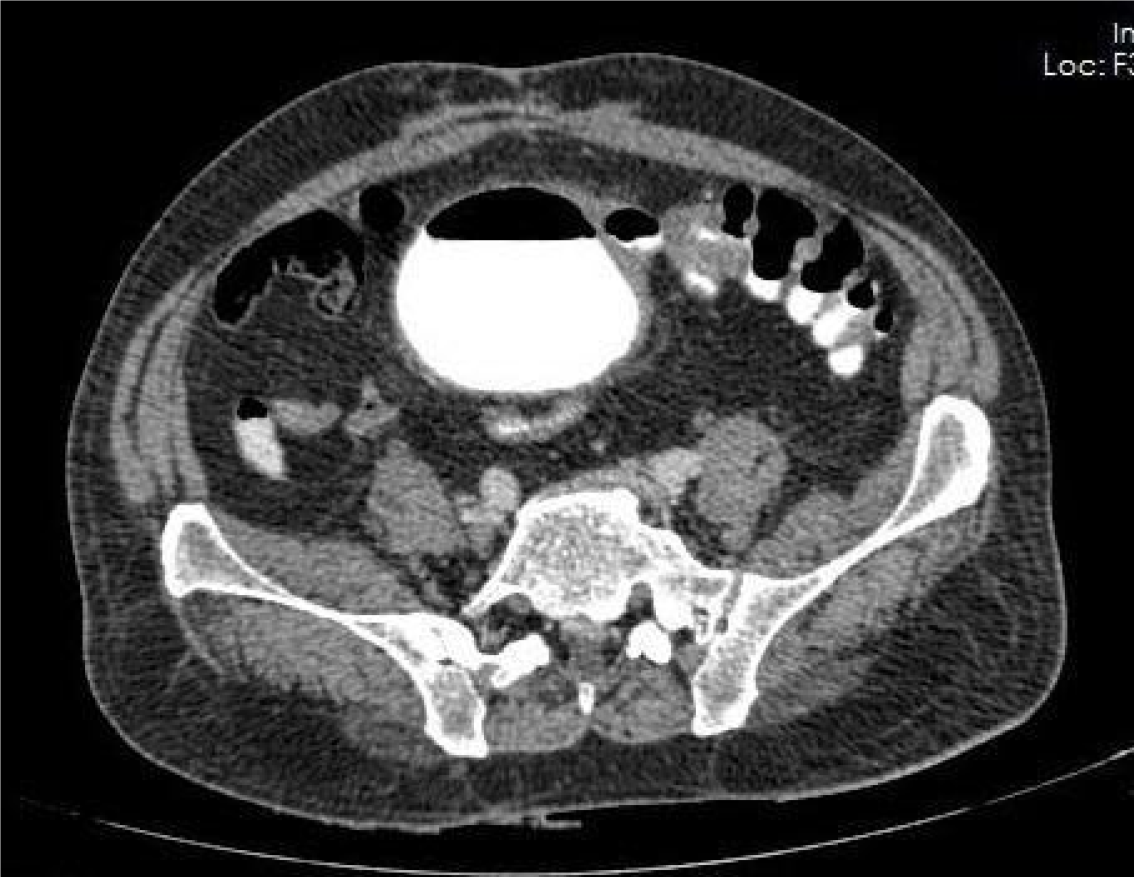

Figure 1

Computed tomography scan showing colovesical fistula between sigmoid colon and bladder (note the presence of gas within the bladder and communication with the sigmoid colon).